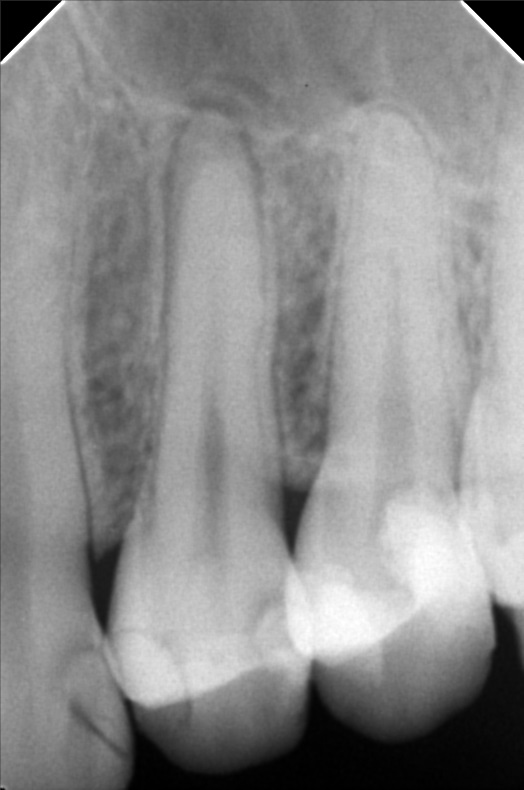

Edit Record Check our patient data records. Add patient information Patient Info Profile picture Last Name First Name Middle Name Birthdate Age Street Barangay City Country Zip Code Contact number Email Procedure 10/13/21- 26 LC with MTA MOD 23 Lingual Distal 11/24/21 - 25/27 LC# 27 #15 IRM -/Xray 03/16/22- zircinia prep on 15/16 shade: a3 body, cervical b3 digital impression done temporary crown done LC mesial 15, distal 14 xray on 24 3/25/22- installation 15, 16 zirconia opening of canal 24 TF with EUgenol 03/30/22 Lingual 18/ Buccal 19 Formocresol Incision and drainage Laser rx: co amoxiclav 625 mg/ mefenamic 500 mg 04/29/22- lingual 16.5mm buccal 19mm 05/04/22- obturation/ LC 8/12/22 - tooth prep #24 8/18/22- Cementation zirconia crown #24 8/26/22 - xray, intraoral radiograph 05/12/23- OP(L) 05/19/23- Xray/ Ozone/Resto - #21(mesial & lingual) 09/10/24 OP w/ air polisher 07/19/25 op with air polisher + fluoride 03/18/26 OP 04/08/26 #48 - Occ mesial MTA Fiber Biomimetic File delprado26.jpg File 2 delprado23-24-25.jpg File 3 6afb059c-2de8-4dc8-ac4d-ae6435b6dabc.jpeg File 4 katherine_del_prado.jpg File 5 katherine_del_prado_02.jpg File 6 katherine_del_prado_03.jpg File 7 File 8 File 9 File 10 File 11 File 12 File 13 File 14 File 15 File 16 File 17 File 18 File 19 File 20 Retain Record Retain Record Yes No Save Your Changes